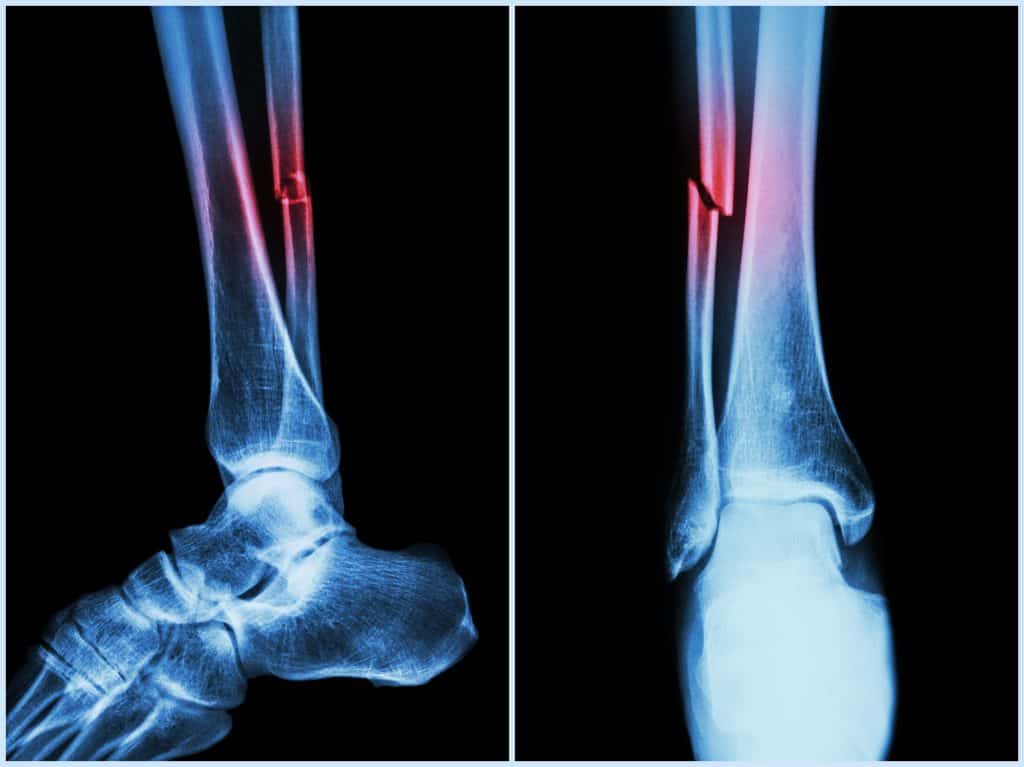

Ozljede fibule najčešće se javljaju kod nekih sportskih ozljeda, odnosno, nastaju kao rezultat prekomjernog istezanja što osim istezanja mišića i osjećaja nelagode može dovesti i do toga da se pokidaju sindesmotski ligamenti ili pak ligamenti na području skočnog gležnja. Prilikom nezgodnih padova ili udaraca može doći i do pucanja fibule, no ovisno o tome gdje kost pukne može se pričati o prijelomu glave fibule ili frakturi tijela fibule. Ukoliko fibula pukne na ijedan način, tada se rade imobilizacije koje pomažu zacjeljivanju kosti, no prije toga potrebno je napraviti pretrage kao što je rendgen nogu i slično. Fibula u rijetkim situacijama može biti pogođena tumorima, koji mogu biti benigni ili zloćudni te oni mogu pritiskati neke živce zbog čega može doći do paralize. U slučajevima kada sumnjate na lom ili neku drugu bolest fibule izrazito je važno posjetiti liječnika kako bi se mogla napraviti liječnička intervencija pomoću koje će kost ponovno natrag srasti ili pomoću koje će se ukloniti tumor te se na taj način omogućiti ozdravljenje.